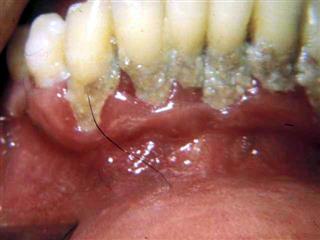

Gencive enflammée, spongieuse, d'aspect scorbutique, ulcérée, saignant facilement, avec une salivation abondante, irritante, fétide et souvent sanguinolente. Parodontopathies évolutives.

Dans ce contexte général, il y a d'abord une gingivite rapidement ulcéreuse avec des douleurs variables, pires la nuit, accompagnée d'une hypersalivation surtout nocturne, au point de tacher l'oreiller. C'est donc un tableau clinique qui évoque MERCURIUS SOLUBILIS, remède complémentaire, aussi bien aigu que chronique. L'aggravation se fait vers une parodontopathie rapidement mutilante, avec des poches suppurées (MERCURIUS), des ulcérations profondes, le tout aggravé par une hygiène buccale ou générale décevante, souvent inexistante.